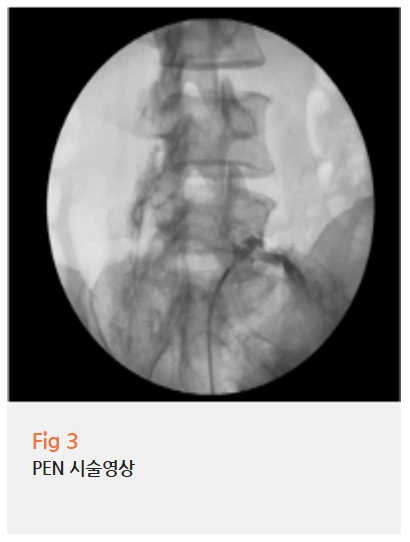

우선 전방전위증으로 인한 신경협착에 대해서는 PEN 시술을 진행했습니다.

PEN(Percutaneous Epidural Neuroplasty)은 척추 신경 주변의 유착과 염증을 직접 풀어주는 시술이에요.

단순히 약물을 주입하는 것이 아니라,

가느다란 카테터를 경막외강으로 진입시켜 협착된 신경 주변을 직접 처치하는 방식입니다.

일반적인 신경차단 주사와는 접근 방식이 다르고, 그래서 효과 면에서도 차이가 나는 편이에요.